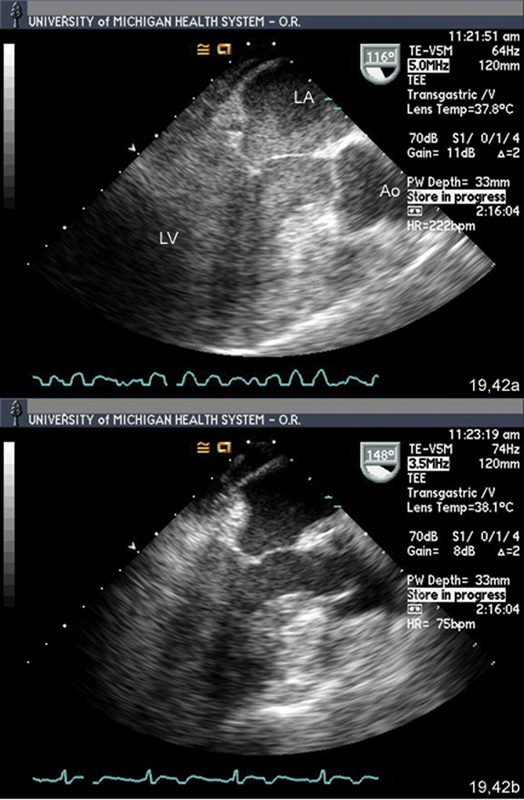

فحوصات تشخيصية لبعض امراض القلب والشرايين التاجية